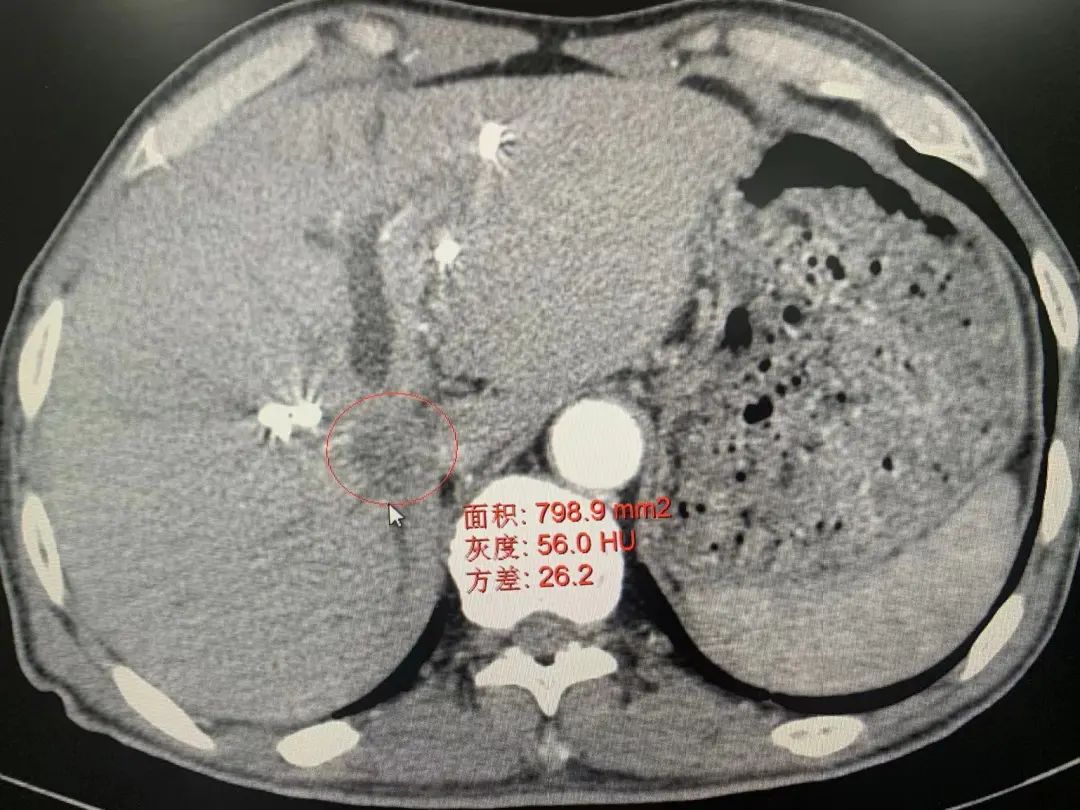

患者術(shù)前影像資料